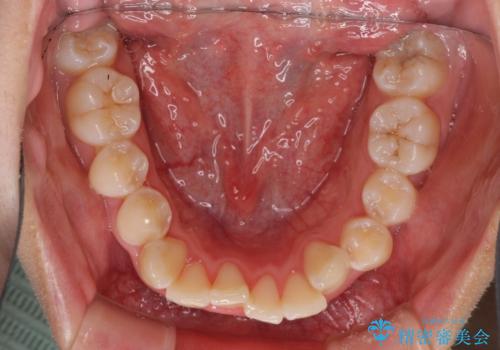

- 骨格的な咬み合わせのズレ、前歯のデコボコとクロスバイトを気にして来院された患者様です。

口元の突出感が若干あり口が閉じにくく、デコボコが強いため、上下左右の小臼歯計4歯を抜歯し、ワイヤー装置による矯正治療を行うこととしました。

また、舌の突出癖が強く、下顎前歯が前方に押し広げられる可能性が高いため、舌癖の改善を継続的に行うよう指示しました。

治療中に舌の突出癖が改善されず、下顎前歯が著しく前方に突出して反対咬合となってしまう局面がありました。

アンカースクリューを使用しながら舌癖の改善を図り、何とか咬み合わせを改善することができました。